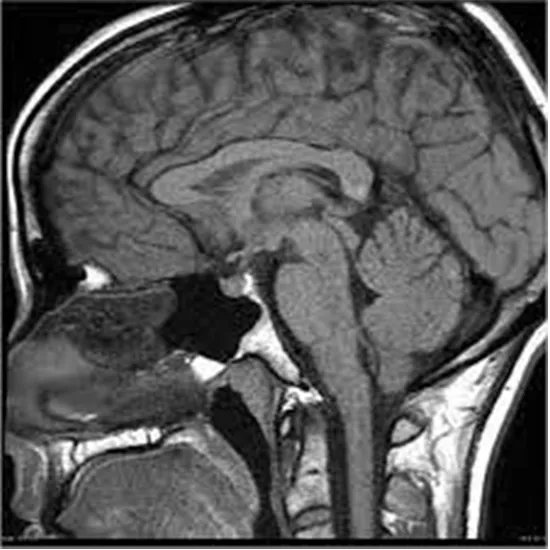

MRI of the pituitary is an imaging procedure that is useful to check the pituitary gland in the brain that regulates the hormones of the other glands.

Magnetic resonance imaging of the pituitary gland helps in the identification of the disorders related to the pituitary gland, like determining its shape, size, shape, injury, etc. The MRI scan creates high-contrast images of the scan that aid in the diagnosis.

Generally, the MRI scan is preferred for image production of the pituitary gland as the MRI scan holds superiority in the definition of the soft tissues in the sella turcica bone. The MRI scan can detect even the tiniest lesions pertaining to the pituitary gland soft tissues.

The MRI pituitary scan is considered the best scan for finding tumors or cancers of the pituitary gland. This imaging technique operated using radiowaves and strong magnets. The scan images produced in the scanning technique help in determining abnormalities in the structures of the gland, thereby helping to nake the diagnosis.